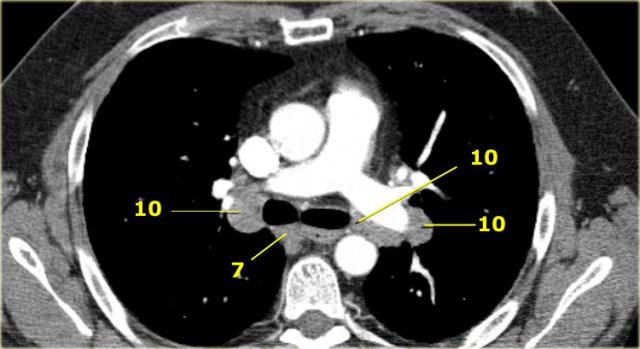

10. Hilar nodes

These include nodes adjacent to the main stem bronchus and hilar vessels.

On the right they extend from the lower rim of the azygos vein to the interlobar region.

On the left from the upper rim of the pulmonary artery to the interlobar region.

7.Subcarinal

7. Subcarinal nodes

These nodes are located caudally to the carina of the trachea, but are not associated with the lower lobe bronchi or arteries within the lung.

On the right they extend caudally to the lower border of the bronchus intermedius.

On the left they extend caudally to the upper border of the lower lobe bronchus.